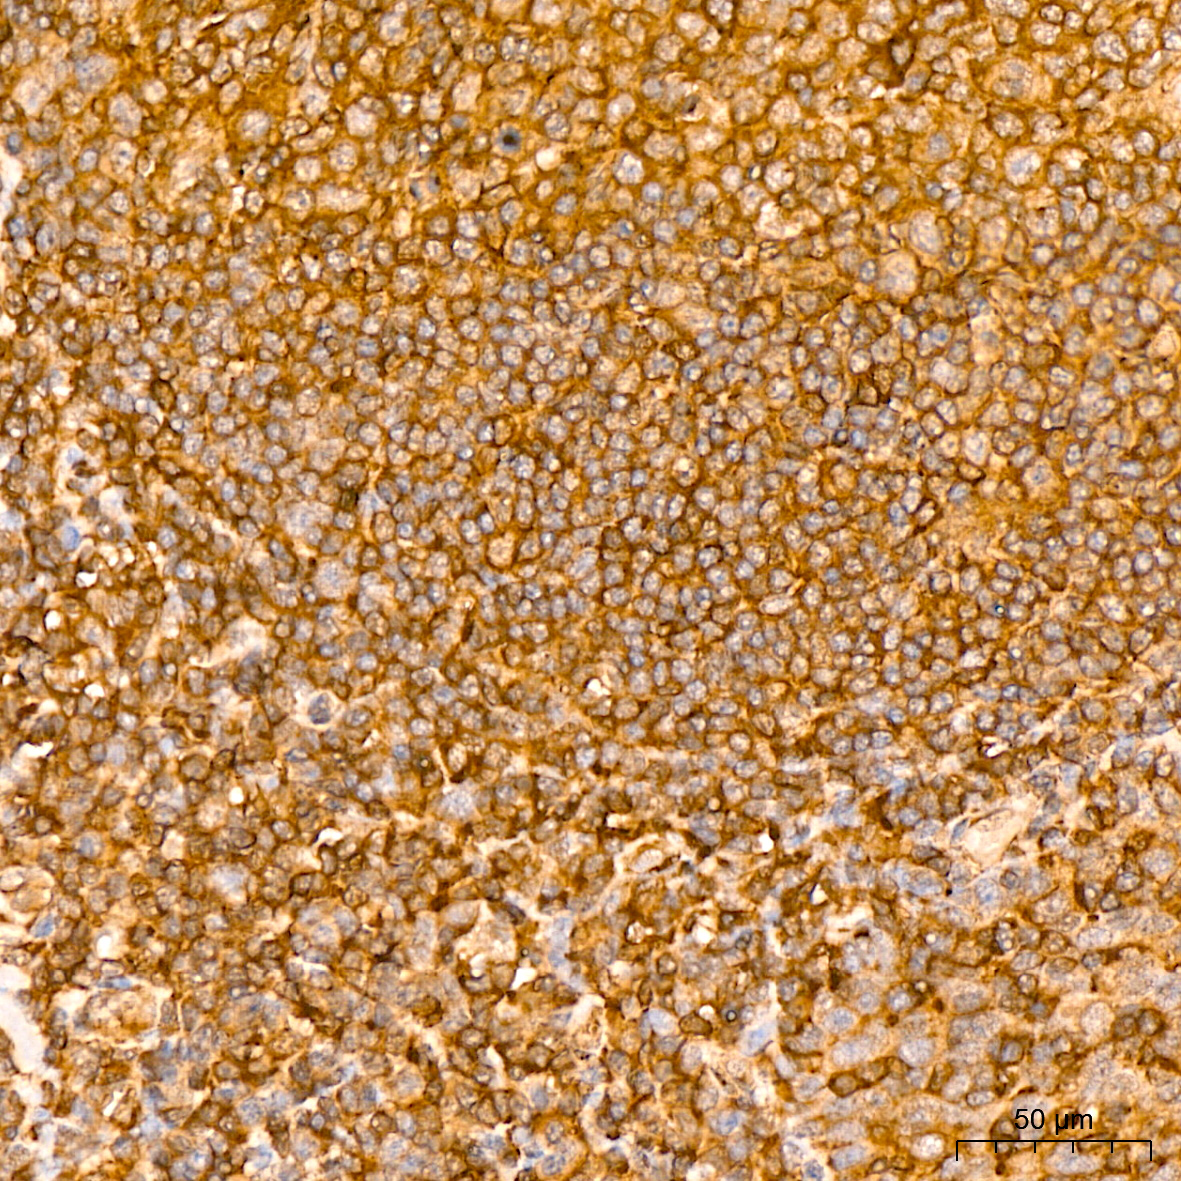

| Immunohistochemistry analysis of paraffin-embedded Human tonsil tissue using NF-kB p65/RelA Rabbit mAb (A19653) at a dilution of 1:800 (40x lens). High pressure antigen retrieval performed with 0.01M Citrate Bufferr (pH 6.0) prior to IHC staining. |